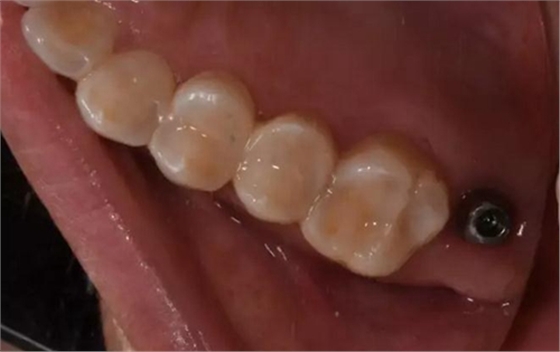

術后口內(nèi)照片

修復體戴入口內(nèi)后照片,與鄰牙鄰接良好。